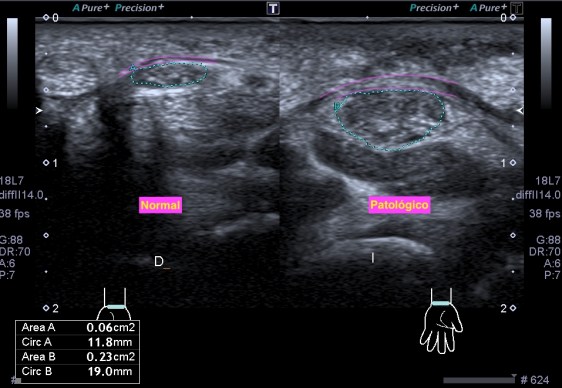

Un breve recuerdo anatómico de la zona tanto en eje largo como en eje corto (longitudinal o transverso), fig 3 y 2 respectivamente, . Fíjese la/el lectora en el posicionamiento del pictograma de referencia.

Acto seguido procedo a las mediciones en ambos planos:

Comprobando los cambios objetivados en la ecoarquitectura del músculo figuras 4 y 5, le pido al paciente que realice contracción del muslo normal y del patológico, observando claros cambios de la ecoarquitectura y de comportamiento en la exploración dinámica.Mira:

El Recto anterior afectado no se contrae correctamente (fig 6), de facto, casi no sufre variación respecto de su situación basal, el normal sufre una hipoecogenicidad aumentada, semiológicamente normal en la contracción (fig 7) y un cambio en su aspecto respecto de la situación de reposo muscular.

Se comprobó que las fibras musculares estaban íntegras (el paciente fue diagnosticado erróneamente al no realizarse prueba de imagen en su visita a urgencias) y el diagnóstico radiológico final fue una alteración del Recto Anterior secundaria a un Síndrome de Denervación Muscular